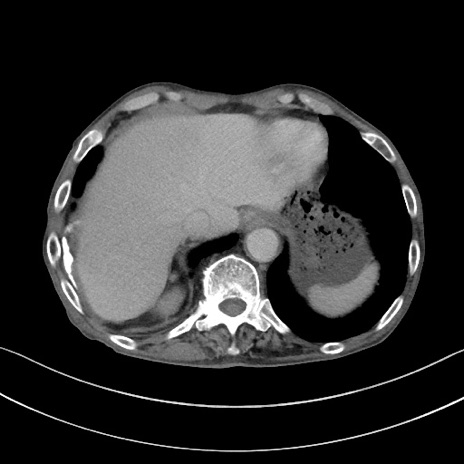

症例3(横断像)

【症例】 70歳代男性

【主訴】右鼠径部腫瘤、疼痛

【現病歴】本日朝より上記主訴あり、受診。

【既往歴】膀胱癌にて膀胱全摘、両側尿管皮膚瘻

【データ】WBC 5600、CRP 0.56